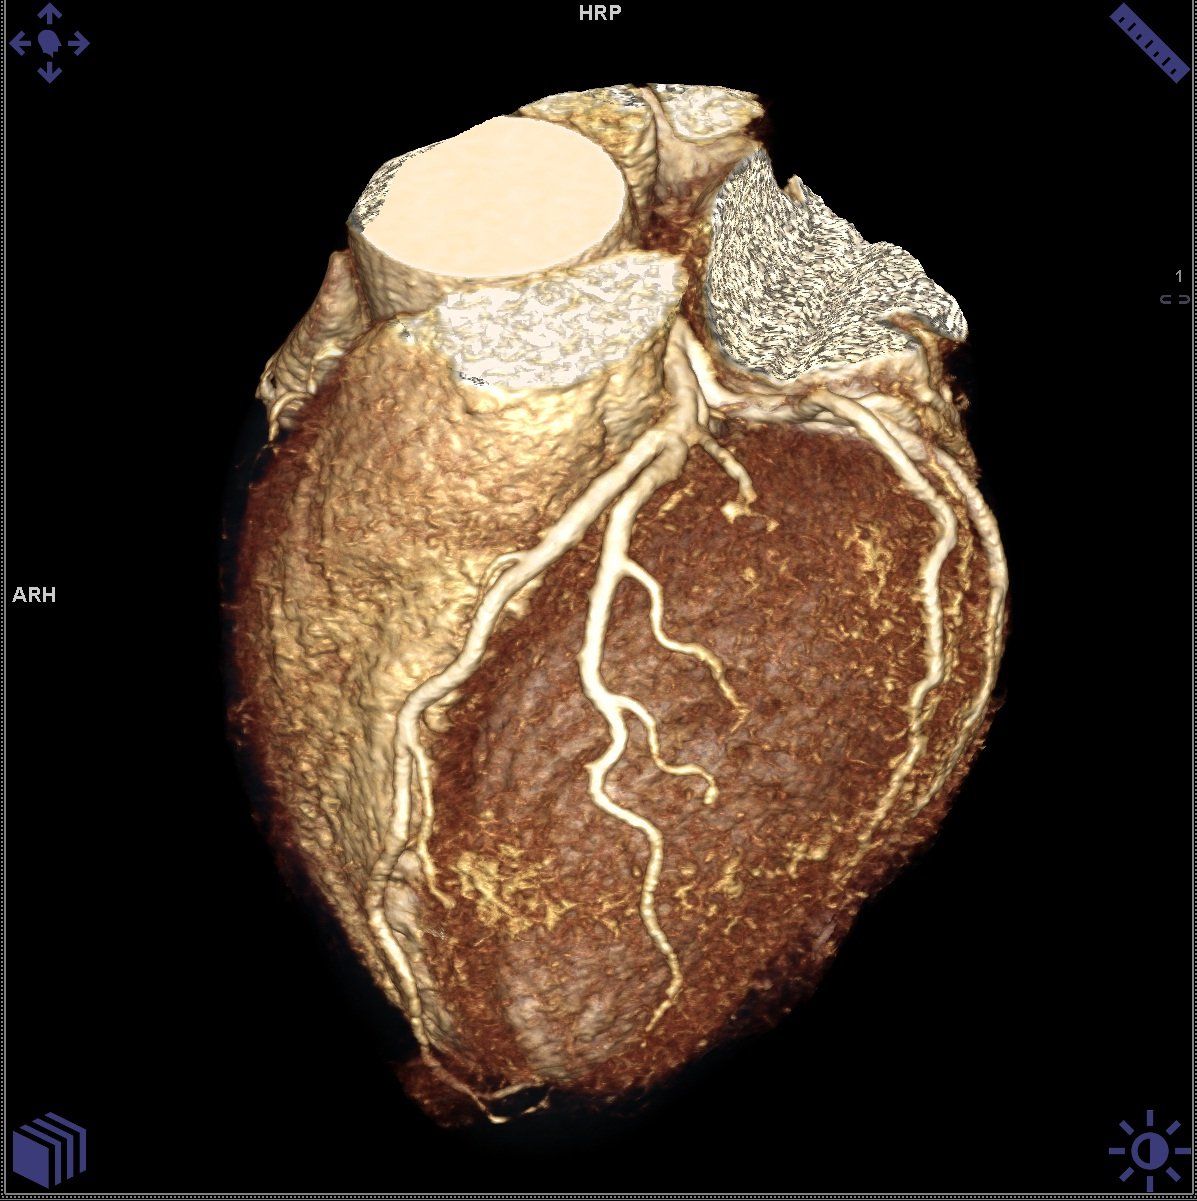

Cet examen réalisé par un radiologue avant une intervention chirurgicale permet au praticien d'être guidé et de voir de façon précise d'emplacement de la zone à intervenir.

Votre scanner aide votre médecin à localiser une lésion ou une anomalie.

Réalisez un scanner prescrit par votre praticien afin de vérifier la présence d'une lésion ou d'une anomalie.